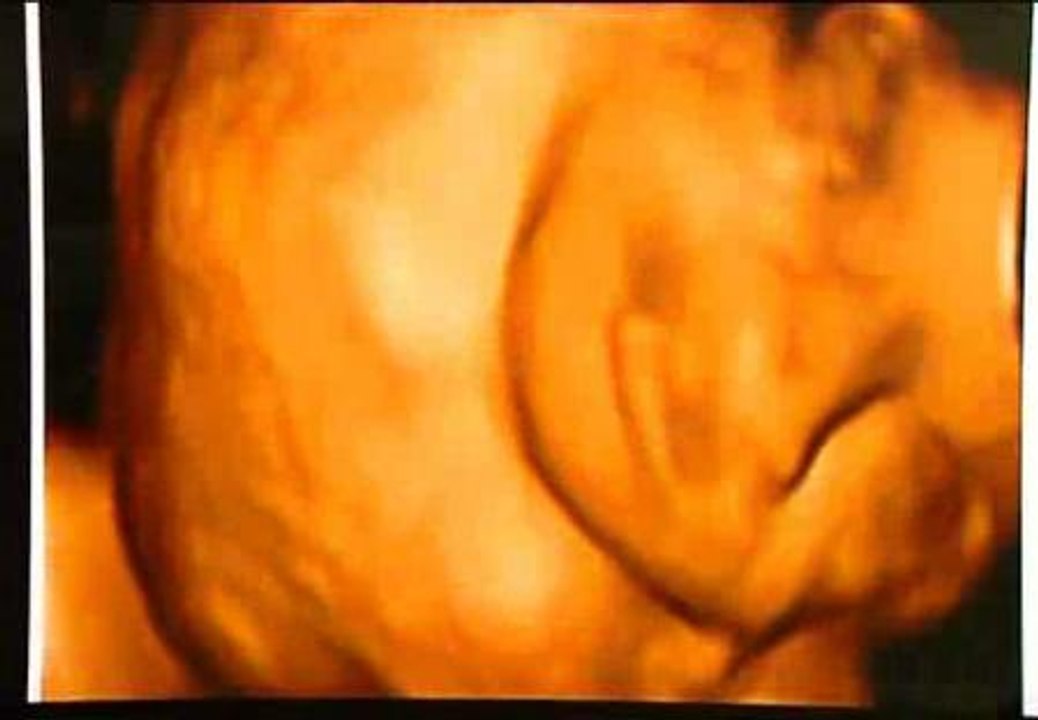

<p>Esther fue operada con &eacute;xito de espina b&iacute;fida en el Hospital Vall d&#039;Hebron de Barcelona cuando ten&iacute;a 24 semanas. Es el primer caso del mundo de malformaci&oacute;n que se repara con un parche sint&eacute;tico reabsorbido por la piel del mismo beb&eacute;. Esta enfermedad afecta a uno de cada 1.000 reci&eacute;n nacidos y se desencadena cuando el feto en desarrollo no cierra por completo la columna vertebral y la m&eacute;dula espinal.</p>